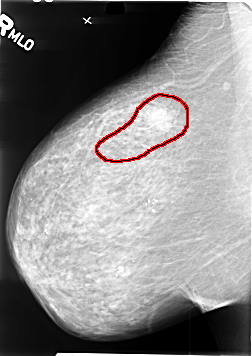

B_3411_1.RIGHT_MLO

RIGHT_MLO LINES 4624 PIXELS_PER_LINE 3272 BITS_PER_PIXEL 12 RESOLUTION 50 OVERLAY

FILE: B_3411_1.RIGHT_MLO.OVERLAY

TOTAL_ABNORMALITIES 1

ABNORMALITY 1

LESION_TYPE CALCIFICATION TYPE N/A DISTRIBUTION LINEAR

LESION_TYPE MASS SHAPE IRREGULAR MARGINS ILL_DEFINED-SPICULATED

ASSESSMENT 5

SUBTLETY 5

PATHOLOGY MALIGNANT

TOTAL_OUTLINES 1

BOUNDARY